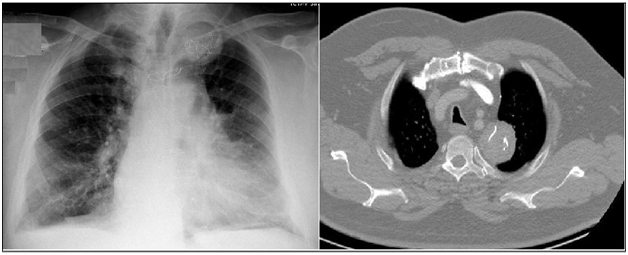

On physical examination, his temperature was 38.5°C, his pulse was 60bpm, his respiratory rate was 16breaths/min, his blood pressure was 135/80mmHg, and his oxygen saturation was 97% on room air. His white blood cell (WBC) count at the time of admission was 15,600/µL. In his respiratory system examination, dullness was detected on percussion in the right middle zone. His auscultation and other system examinations proved normal. A chest X-ray showed a 6cm mass in the right middle zone (Figure 1). A computerized tomography (CT) scan of the thorax showed a 6x8cm2 homogeneous soft tissue mass in the right hemithorax adjacent to the pleura, suggesting a diagnosis of empyema or lung abscess.

Figure 1 Posteroanterior chest X-ray (a) and CT of the thorax (b) showed a 6x8 cm2 homogeneous soft tissue mass in the right hemithorax adjacent to the pleura.